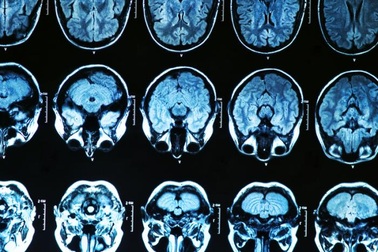

Bệnh Alzheimer được chẩn đoán như thế nào?Để chẩn đoán sa sút trí tuệ Alzheimer (bệnh Alzheimer), các bác sĩ sẽ đánh giá các dấu hiệu và triệu chứng và tiến hành một số xét nghiệm.

10 dấu hiệu cảnh báo sớm bệnh AlzheimerBệnh Alzheimer là dạng sa sút trí tuệ phổ biến nhất - một loại rối loạn não ảnh hưởng đến cuộc sống hàng ngày do mất trí nhớ và thay đổi nhận thức. Có ba giai đoạn chính của bệnh Alzheimer: nhẹ, trung bình và nặng.